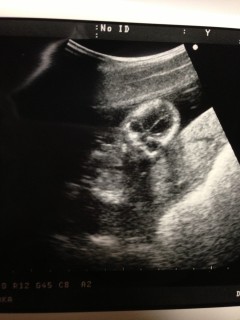

こんばんは。今日で五ヶ月になり診察にいきました。エコー写真を撮って頂いていると始めはうつ伏せになっていましたが3秒間程横向きになった時に、股あたりに白い丸い物が二つ見えました。男の子なのかな?わかる方いらっしゃいませんか?

こっちを向いている写真です(^_^)

うわっ!!めっちゃこっち見てる・・